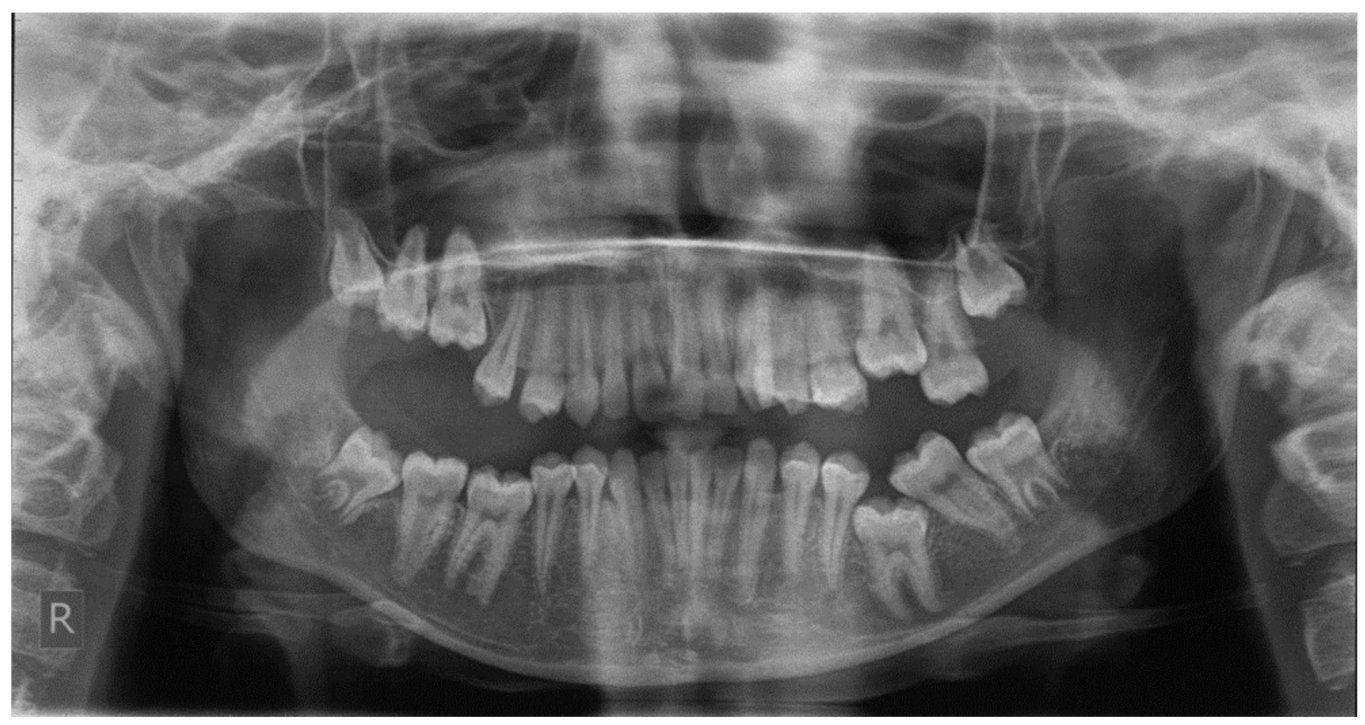

PFE attributes combine elements that resemble both primary and secondary retention (Figure 4). The diagnosis of PFE is impeded to a great extent by the complexity of this clinical picture (Figure 5 and Figure 6). It appears that this clinical condition has two different mechanisms or two different aspects of the same mechanism since the tooth may erupt in its initial position and thereafter stop its further eruption (a clinical condition known as secondary retention) [7,8,14], or the tooth may not be able to erupt at all [11]. In this context, a definitive diagnosis of PFE cannot easily be decided, as it is possible that PFE presents two separate mechanisms [11] or two independent manifestations of the same mechanism. Only if we were to examine an environment where genetic, pathological, and environmental factors—all factors potentially responsible for the discontinuation of the tooth’s eruption—are absent would a PFE diagnosis through a retrospective examination be possible.

Figure 4.

Patient’s orthopantomography presenting Primary Failure of Eruption in all four dental quadrants.

Figure 5 and Figure 6 present a PFE case of a 17-year-old female patient referred to the Orthodontic Clinic of the Dental School of the National and Kapodistrian University of Athens, Greece. Clinical examination showed a posterior open bite on the right segment, as well as infraoccluded left upper and lower first molars. The patient’s orthopantomography shows no visible PDL of the right upper and lower first molars or the teeth distally related to them.